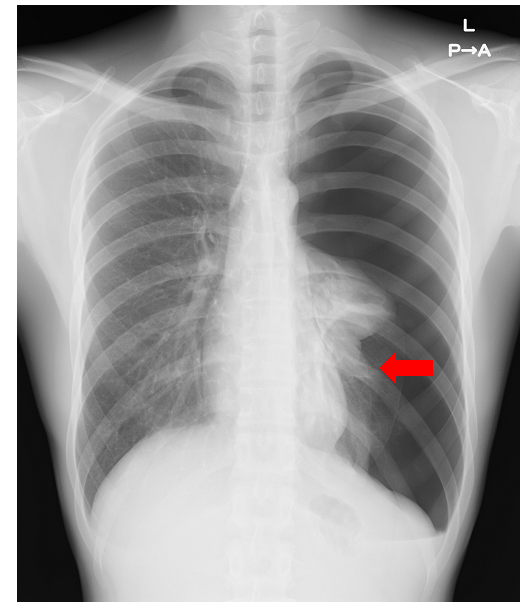

左気胸の胸部レントゲン写真。矢印は気胸により虚脱した肺を示しています。

肺とその入れ物である胸郭に囲まれた部位を胸腔と言います。気胸とは肺から空気が漏れて、胸腔に溜まっている状態をいいます。この時、漏れた空気は肺を押すため肺は伸展できなくなり息が苦しくなったり、胸郭側(肺には痛みの神経はありませんので、痛むのは胸壁側です)に痛みが出たりします。手術では、1〜3つの小さな創から胸腔鏡下に、空気が漏れる原因となっている肺の一部を切除したり(部分切除)、空気もれの再発を予防するために肺表面を吸収性シートで補強したりします。術後2〜3日で退院できる方が多いです。